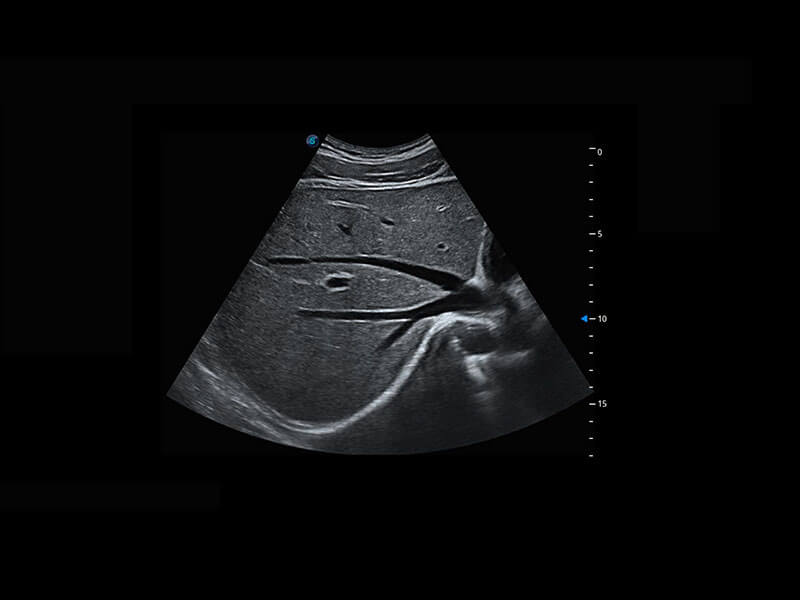

早孕筛查

P60在胎儿早孕期超声筛查中为您带来优异的图像质量。

• 早孕-胎心

• 高分辨率容积成像-早孕胎儿

• 胎儿体循环

• 光影成像-孕囊